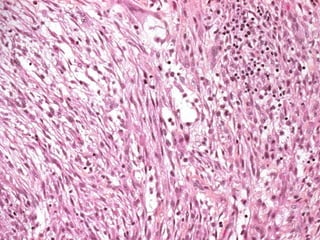

TheThe storiform-pleomorphic type is the moststoriform-pleomorphic type is the most

commoncommon and as the name indicates isand as the name indicates is

composed of malignant spindle cells oriented incomposed of malignant spindle cells oriented in

a storiform pattern with scattered, large rounda storiform pattern with scattered, large round

pleomorphic cells .pleomorphic cells .

Malignant fibrous histiocytoma revealing fascicles ofMalignant fibrous histiocytoma revealing fascicles of

plump spindle cells in a swirling (storiform) pattern,plump spindle cells in a swirling (storiform) pattern,

typical but not pathognomonic of this neoplasmtypical but not pathognomonic of this neoplasm